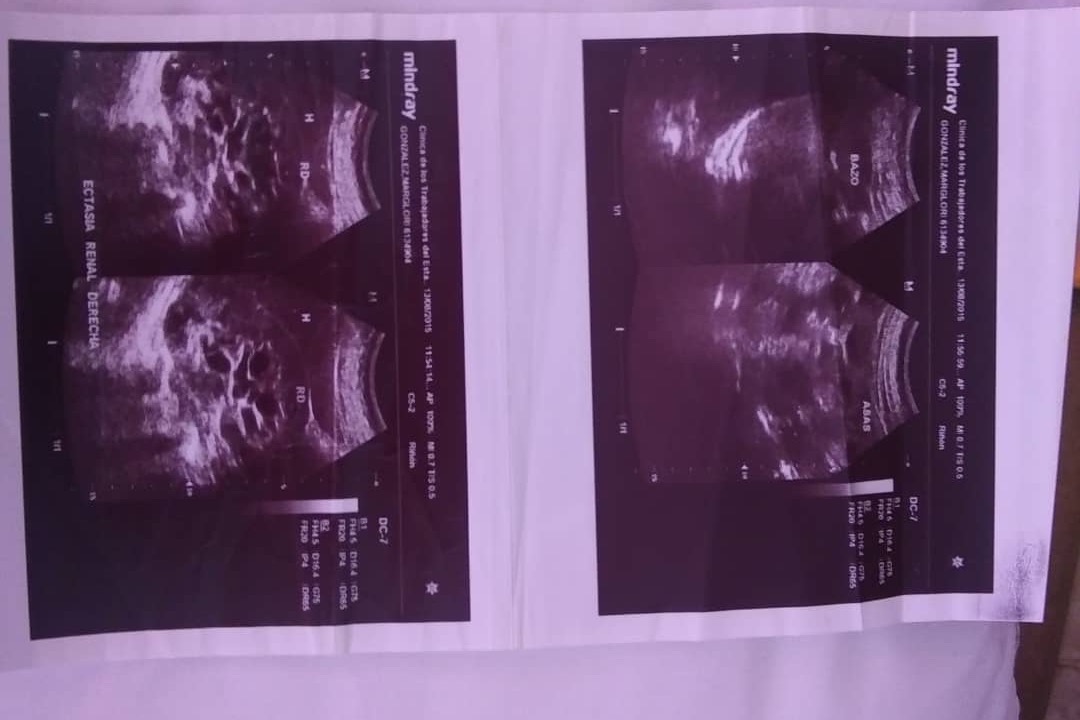

Soy un paciente con riñon único derecho.

Y me diagnosticaron quistes parapielicos derechos y pielocaliectasia derecha.